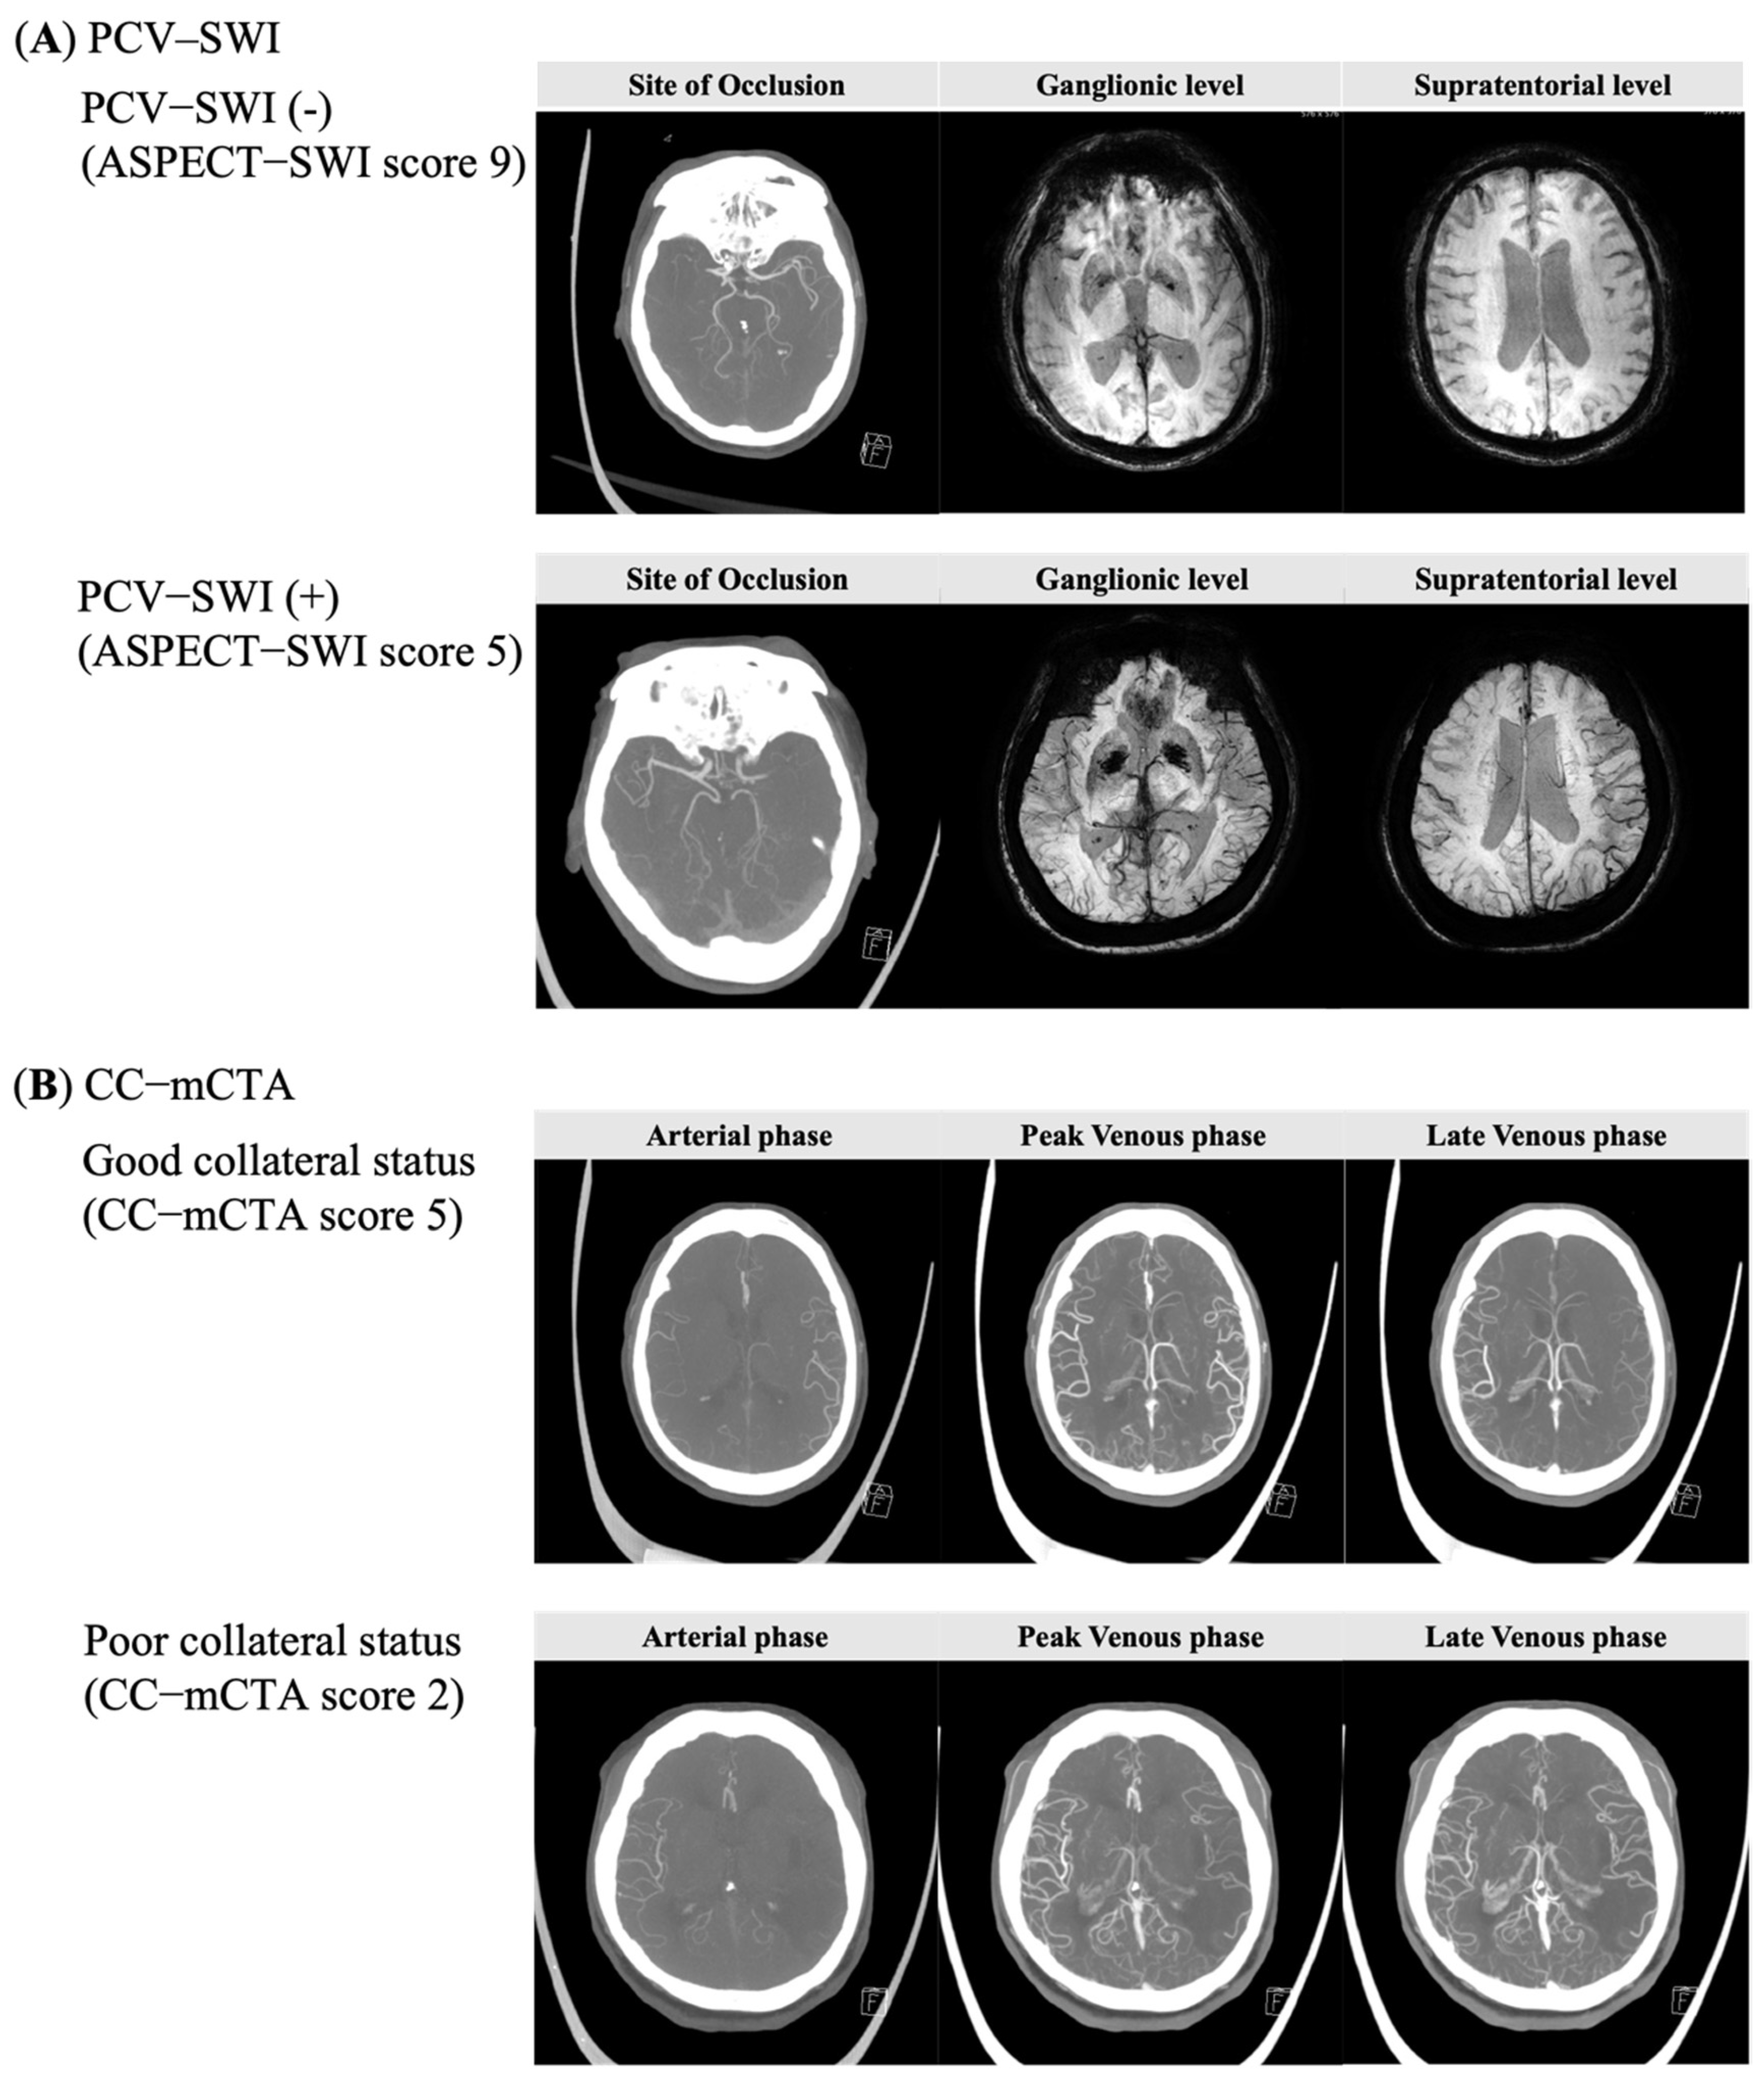

2.2. Imaging Analyses